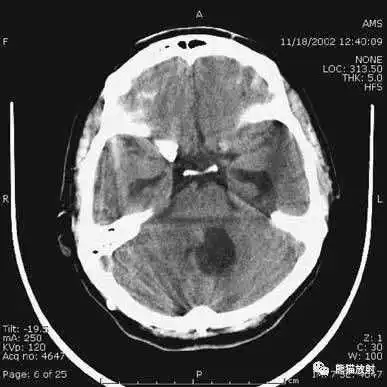

高血压性脑出血:

- 自发性出血;

- 继发于长期高血压及慢性血管病;

- 常见于基底节区、丘脑、脑桥、小脑。

A:占位效应,相邻脑沟、脑池消失;

F:脑出血破入四脑室。

▲

钩回疝:

是当代偿机制不能适应占位性病变时的结果。

基底节区大量高血压性脑出血,破入脑室及蛛网膜下腔,周围水肿,脑干周围空间消失;脑干出血、脑积水。